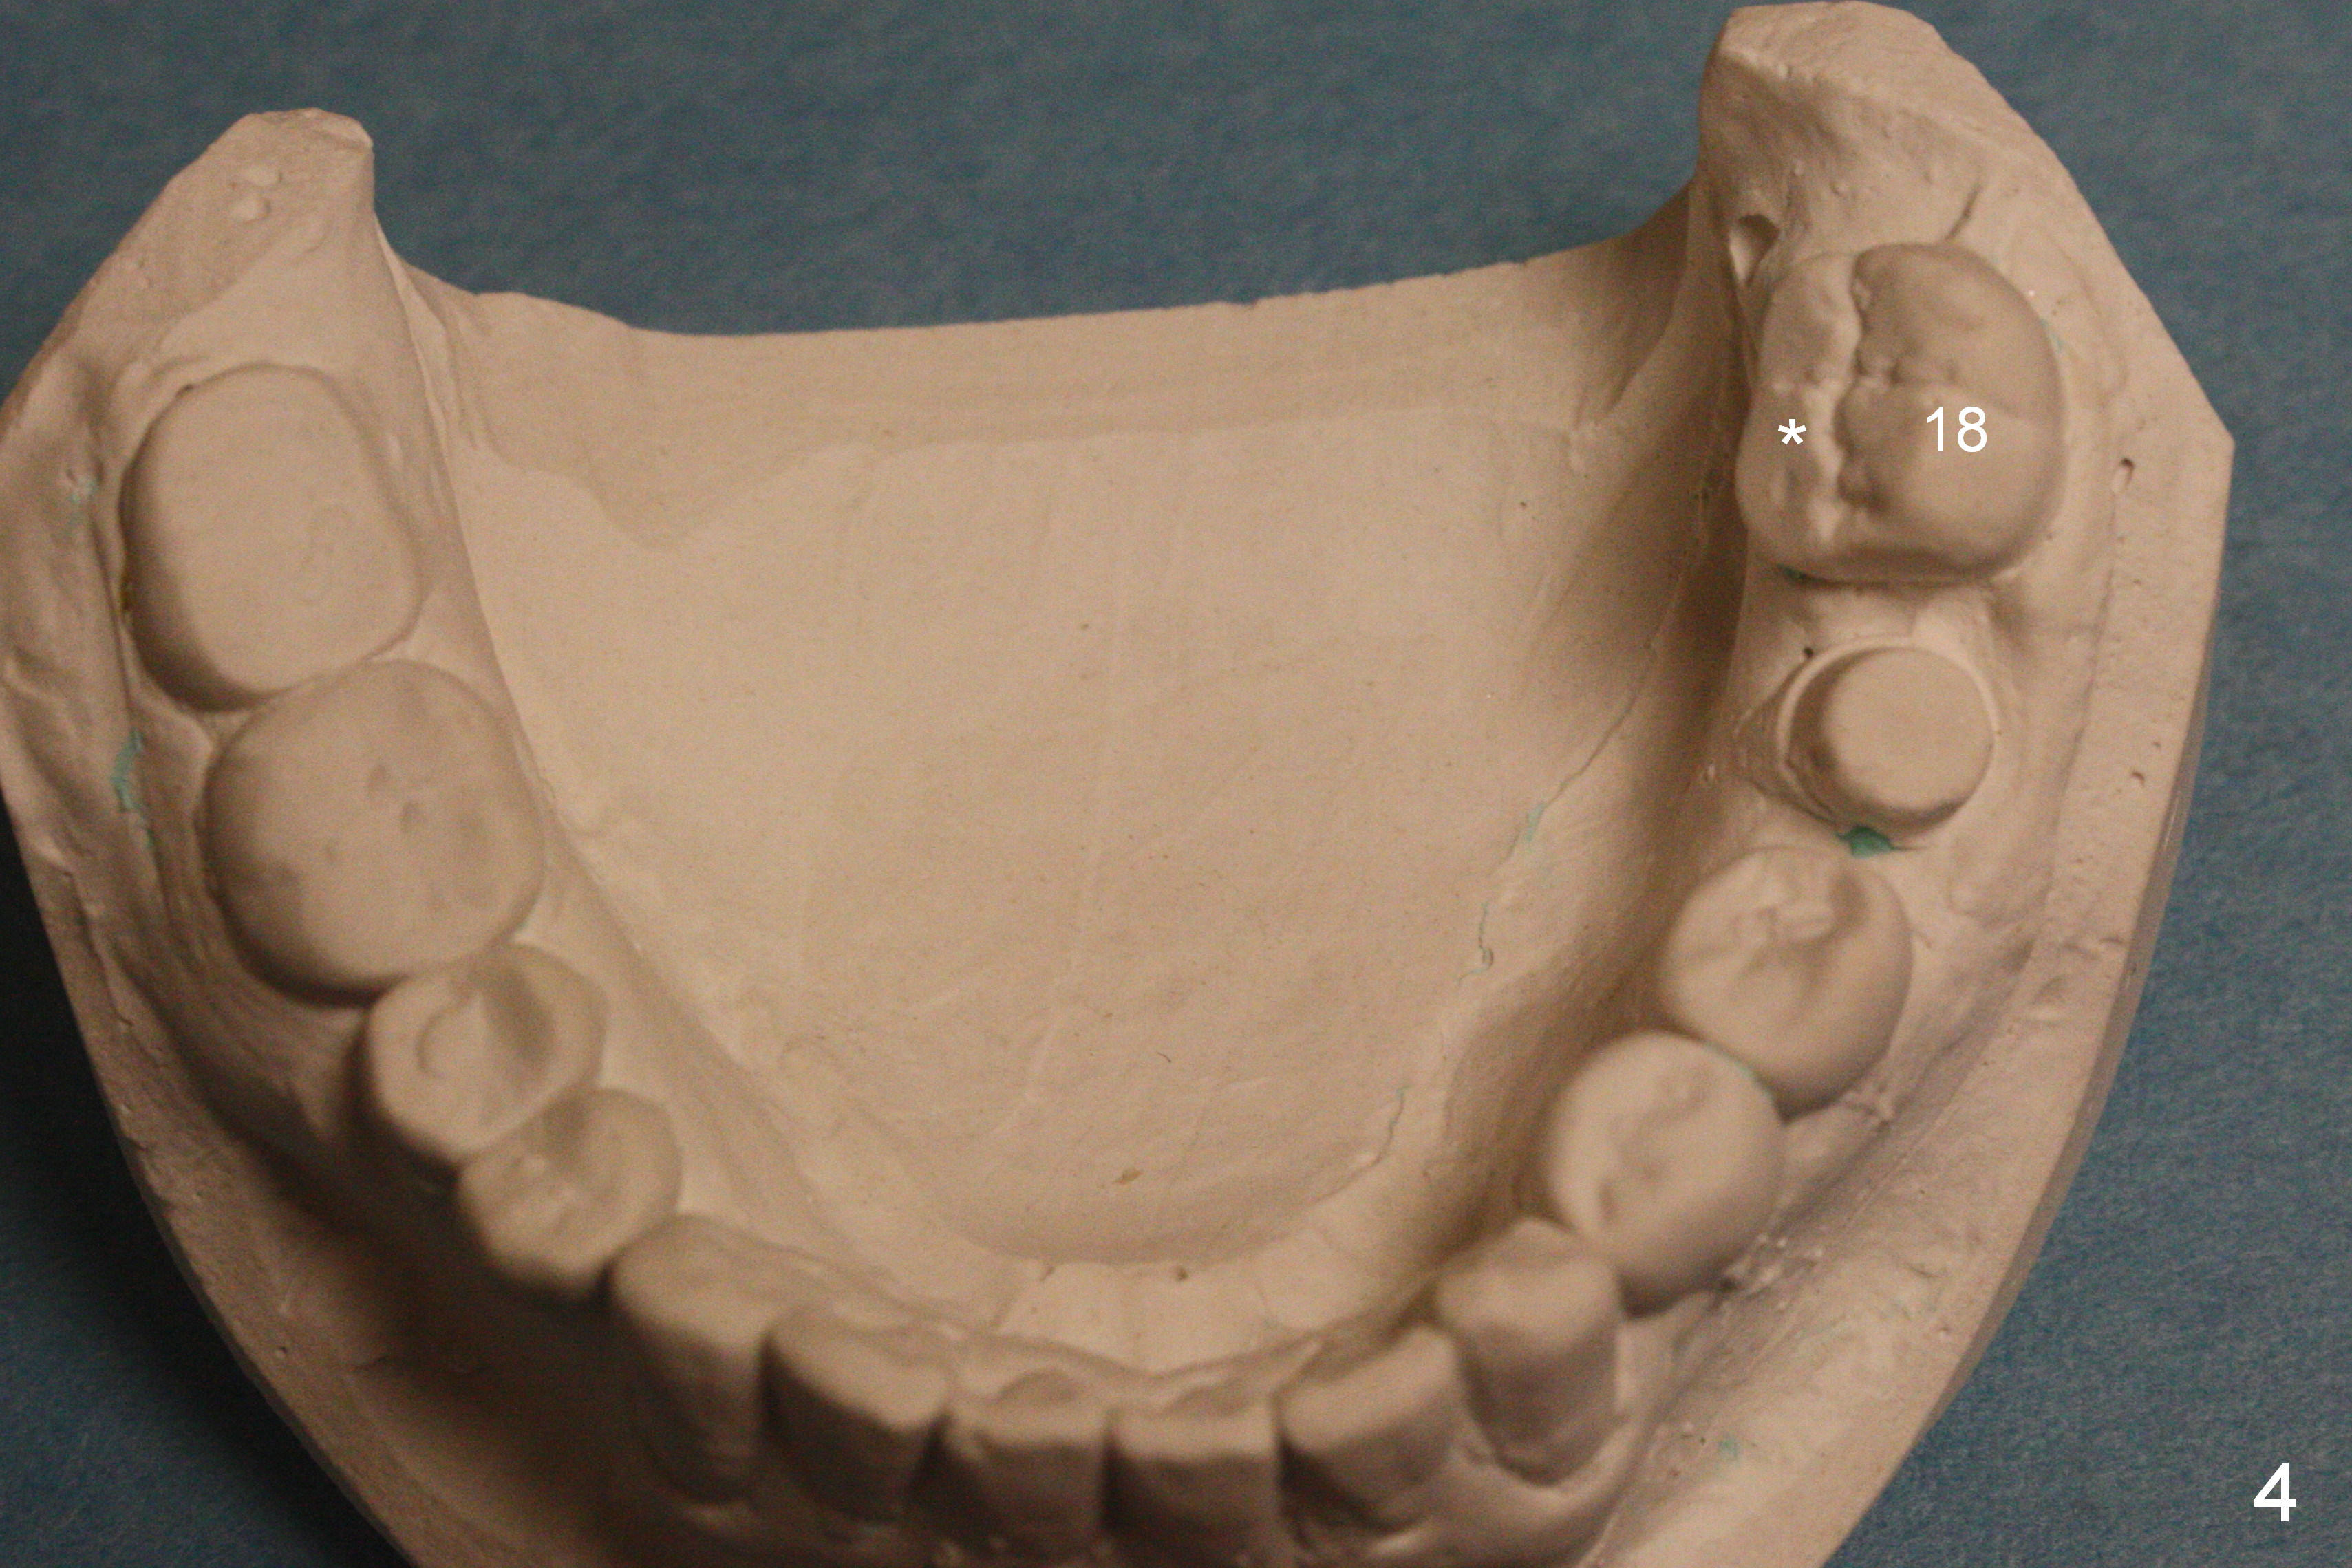

A 40-year-old man had automobile-related mandibular fracture and surgical reduction several years ago. Since then there has been cross bite in the left molar region (Fig.1-2) with abnormal wear facets in the occlusal surface of the teeth #14, 15 and 18 (Fig.3,4 *). At the time of implant placement at #19, the patient reports tooth sensitivity at #15 and wonders whether increase in the occlusal surface of the future crown at #19 can alleviate the tooth sensitivity or not. In fact the tooth #14 and 19 were in cross bite when the sites of #20 and 21 were processed for implant crowns (Fig.1). The cross bite of the left molar area appears to be so severe that surgical segmental osteotomy or orthodontic treatment is required (Fig.5-7).